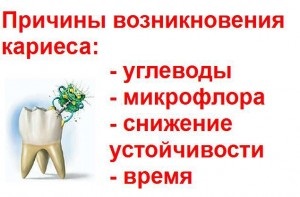

Okai fogszuvasodás

Fennállása alatt a fogászati vizsgálták, és találtam egy csomó különböző elméletek, hogy támogassa a kialakulását és fejlődését a fogszuvasodás. Rögtönzött akkor feltételezhetjük, hogy az elméletek valahol a 400, de nem mindet elfogadták.

Ma, a legérdekesebb az az elmélet Miller, egy modern fogalom, kiegészítve más elméletek. Elmélete szerint, a kölcsönhatás a mikroorganizmusok okozó fogszuvasodás és a szénhidrátok található a szájüregben. Fermentációs élelmiszer elősegíti a kialakulását a szerves savak, amelyek az elején a fogszuvasodást.

Minél nagyobb a sav a szájban, annál inkább erodálja a fogzománcot. Tooth kezdi elveszíteni a kalcium, ami a fogszuvasodás.

Miller különválasztják és további okai a fogszuvasodást. A legérdekesebb az, hogy ő nem csak ajánlott, és előadott különféle elméletek, de a gyakorlatban megerősítette a feltételezést. Miller elméletét tartalmaz számos ellentmondást. De mégis, a modern koncepció nem utasítja el az elmélet Miller és úgy, mint egy alapot, és arra utal, hogy az oka a fogszuvasodás a pH változását különböző részein a fogat, magában foglalva a lepedéket.